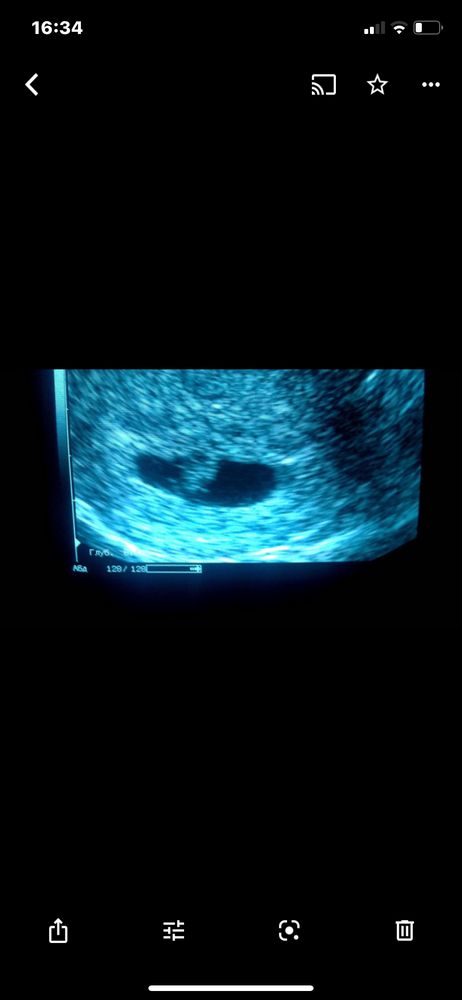

Плодное яйцо

плодное яйцо стало вытянуто,сказал это нехороший знак,что может означать зб

видит маленькую точку в плодном яйце,но это ни о чем не говорит.

Дал проценты на удачную беременность 50/50